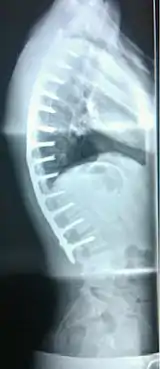

Scheuermann's disease on lateral Xray of the T spine | |

Scheuermann's disease is a self-limiting skeletal disorder of childhood. Scheuermann's disease describes a condition where the vertebrae grow unevenly with respect to the sagittal plane; that is, the posterior angle is often greater than the anterior. This uneven growth results in the signature "wedging" shape of the vertebrae, causing kyphosis. It is named after Danish surgeon Holger Scheuermann.[3][4][5]

Diagnosis is typically by medical imaging. The degree of kyphosis can be measured by Cobb's angle and sagittal balance.